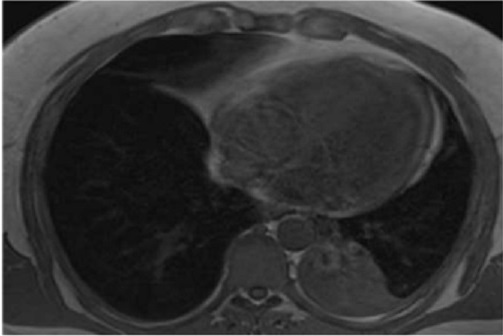

Aspect radiologique IRM thoracique

de cette tumeur en coupe axiale pondérée T1 .

Elle est isointense predominance de heterogene et

zone de hypersignal graisseuse . Image radiologique

IRM ponderee T1 en coupe axiale |